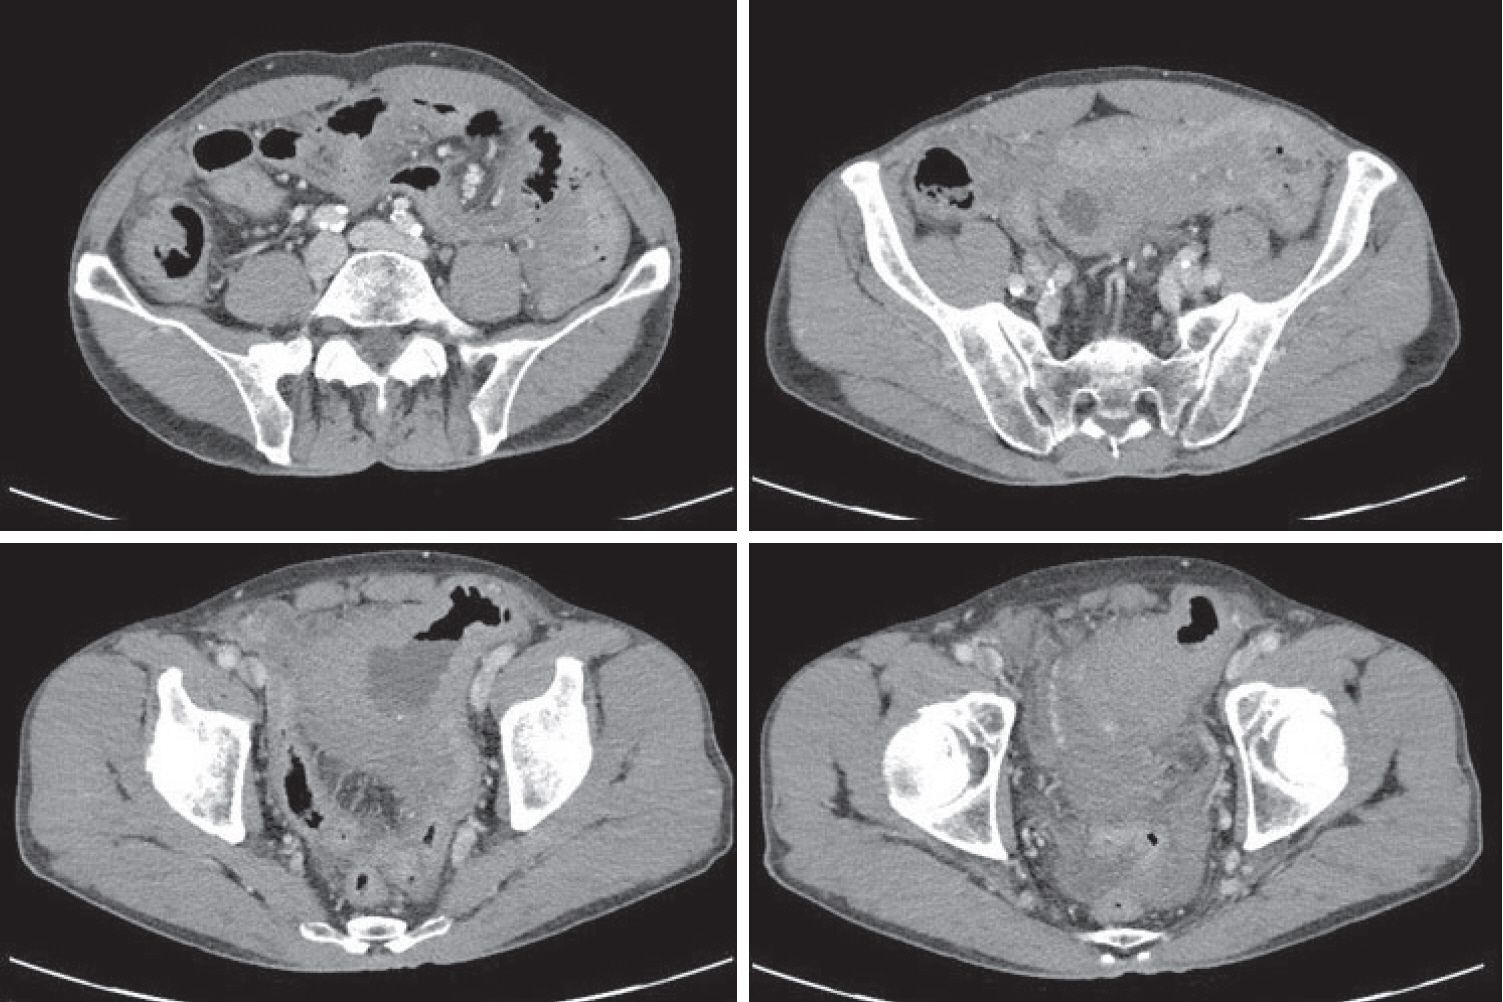

Figure 4.

Subsequent abdominal computed tomography (CT) showing an approximately 9-cm cavitary lesion in the small intestine, abutting the sigmoid colon and urinary bladder dome.

A 70-year-old male underwent sigmoidoscopy after a routine computed tomography (CT) examination, which showed thickening of the sigmoid wall (Fig. 1). Sigmoidoscopy revealed a colonic ulcer, and a biopsy was performed. The lesion was identified as a tubular adenoma; therefore, the patient was referred to the gastroenterology department for repeat biopsy and additional tests. The patient’s medical history included high blood pressure and alcoholic hepatitis. His social history showed that he drank 0.5-1.0 bottle of soju daily and was never a smoker. Information regarding his family history was excluded from the study. The patient had no gastrointestinal symptoms such as abdominal pain or diarrhea, and physical examination findings were unremarkable. Although the biopsy showed a tubular adenoma, the initial colonoscopy indicated that the gross margin of the ulcer was irregularly shaped (Fig. 2), raising suspicion for malignancy. Therefore, despite being asymptomatic, the patient was informed, and another colonoscopy was performed 2 months later. The follow-up examination revealed a scarred sigmoid ulcer located 30 cm from the anal verge, which seemed to have improved compared with the previous findings. Re-biopsy demonstrated features consistent with a simple ulcer (Fig. 3). Accordingly, we concluded that this was a benign colonic ulcer with an inflammatory and ischemic cause rather than cancer, and a follow-up CT scan was sche-duled 1 month later. At the follow-up visit 1 month later, the patient complained of abdominal discomfort after eating for a week, which had not occurred before. He denied having fever, chills, nausea, or vomiting. A subsequent abdominal CT scan showed an approximately 9-cm cavitary lesion abutting the sigmoid colon and urinary bladder dome in the small intestine (Fig. 4). This was accompanied by diffuse nodular omentomesenteric infiltration and peritoneal thickening with small ascites. Based on these findings, the patient was suspected to have a malignant tumor, such as scirrhous carcinoma, inflammatory bowel disease, peritoneal carcinomatosis, or peritonitis, and was referred to a surgeon for surgical treatment. The patient was hospitalized immediately. On admission, the patient complained of abdominal discomfort after eating, and mild generalized abdominal tenderness was noted on physical examination. He was hemodynamically stable. Laboratory testing revealed high white blood cell count of 11.45 × 103/μL (normal range, 4.0-10.0 × 103/μL) with a differential of 67.6% neutrophils (normal range, 38.0-75.0), normal hemoglobin of 16.1 g/dL (normal range, 13.0-17.0), normal platelet count of 151 × 103/μL (normal range, 150-400 × 103/μL), and slightly elevated C-reactive protein level of 7.69 mg/L (normal range, 0.0-5.0). Serum electrolyte and kidney function test results were normal. On the 3rd day of hospitalization, the patient underwent laparoscopic small bowel resection. Immunohistochemical analysis of the resected tissue showed positive staining for CD3, CD4, CD8, CD56, and CAM 5.2 (epithelial marker), and a negative staining for CD10, CD20, CD21, and CD30 (Fig. 5). Histopathological evaluation revealed infiltration by small- to medium-sized T-cell with prominent epitheliotropism, consistent with MEITL. The final diagnosis was MEITL, involving the sigmoid colon, urinary bladder, and peritoneum. Postoperatively, the patient developed persistent ileus with progressive ab-dominal distension and loss of bowel passage, necessitating a second emergency surgery on the 20th day of hospitalization. On the 25th day of hospitalization, the Hemovac drainage became purulent, blood pressure decreased, and the patient went into shock; therefore, a third emergency surgery was performed under the suspicion of bowel perforation. On the 45th day of hospitalization, the patient died of refractory septic shock, presumed to be a complication of intestinal perforation.